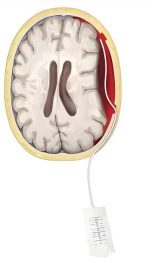

②手术治疗:出血量多,有神经功能障碍的应首选手术治疗,常常采用钻孔引流的手术方式,即在颅骨上钻一个小洞,使颅内的积血排出,并放置一根软管入颅内,留置1-3天使残留的积血持续排出。手术效果往往立竿见影,术后患者精神状态好转,思维变得清晰,乏力的肢体力量得到恢复等。但部分病人可能存在复发的可能,需定期复查;

③介入治疗:也是一种手术,是一种微创手术,这种手术不在头部动刀,而是通过人体的血管进行治疗,我们将在大腿根部穿刺股动脉,通过人体血管将导管输送到头部血管,栓塞病变的血管,从而促进颅内的血肿吸收。适用于不能耐受全麻手术,或不愿意做钻孔手术,或存在钻孔手术禁忌,或血肿反复复发等病人。